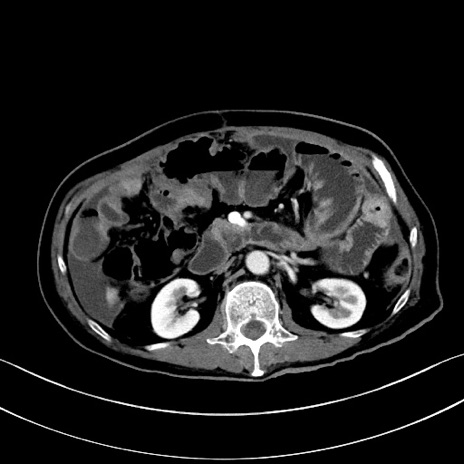

冠状断像

【症例】60歳代男性

【主訴】嘔吐

【現病歴】胃癌にて胃全摘後。食思不振が悪化し、夜中に嘔吐することがある。

【既往歴】胃癌、胃全摘、脾摘、胆摘後

【データ】WBC 5900、CRP 10.56